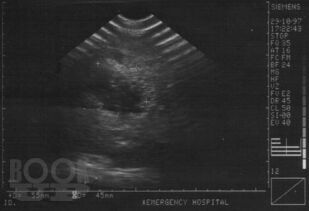

В монографии изложены основные достижения в диагностике закрытой травмы живота, приведены методики УЗИ с описанием эхосемиотики повреждений различных органов брюшной полости и забрюшинного пространства. Включены клинические примеры и большой иллюстративный материал, полученные в процессе собственных исследований. Приведен и аргументирован разработанный на кафедре госпитальной хирургии ВолгГМУ алгоритм диагностики и лечения сочетанной закрытой травмы живота, что определяет выраженную практическую направленность данной рукописи. Монография представляется весьма ценной для студентов старших курсов лечебных факультетов медицинских вузов, клинических ординаторов, практических врачей.